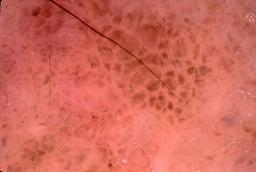

{

"age_approx": 70,

"anatom_site_general": "head/neck",

"concomitant_biopsy": true,

"dermoscopic_type": "contact non-polarized",

"diagnosis_1": "Indeterminate",

"diagnosis_2": "Indeterminate epidermal proliferations",

"diagnosis_3": "Solar or actinic keratosis",

"diagnosis_4": "Actinic keratosis, Lichenoid",

"diagnosis_confirm_type": "histopathology",

"image_type": "dermoscopic",

"lesion_id": "IL_5320579",

"patient_id": "IP_4936244",

"sex": "male"

}